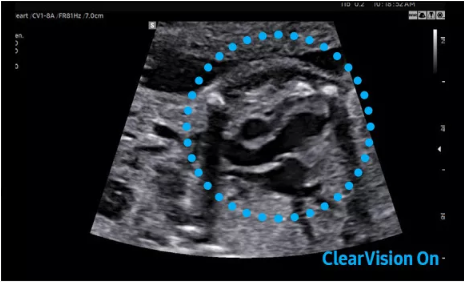

Hera i 10繼承并升級(jí)了全球首款5D超聲“三星麥迪遜WS80A”的“晶體結(jié)構(gòu)”成像理念,即將CrystalBeam?波束形成技術(shù)、CrystalLive?超聲成像引擎、S-Vue Transducer?視覺傳感器集于一身,提供更清晰的圖像。

2D成像方面,Hera i10集成了包括ShadowHDR?、HQ-Vision?、ClearVision等多項(xiàng)具有三星“血統(tǒng)”的技術(shù),加強(qiáng)了圖像的陰影抑制、減少偽影、緩和模糊區(qū)。